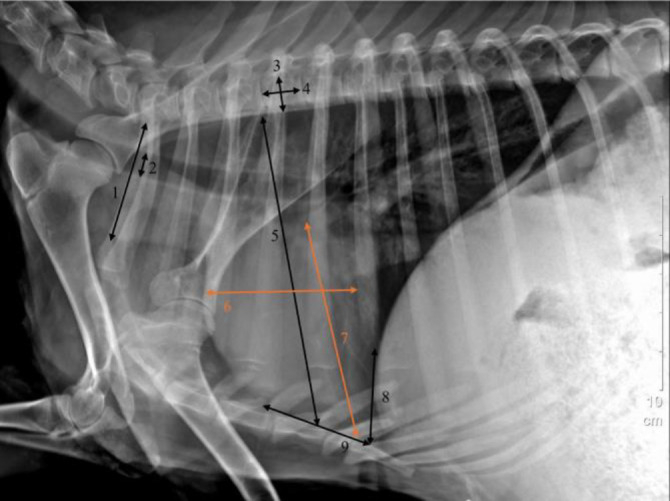

Radiological examination of thorax in Awassi sheep.

Medical imaging methods (magnetic resonance imaging, computed tomography, X-ray, and ultrasound) are used to guide physicians when diagnosing diseases and planning their treatment. Thorax radiography is frequently preferred for the detection of diseases related to the respiratory system and the heart. When the thorax anatomy is known, this facilitates the detection of diseases in these regions. The vertebral heart score (VHS) is a parameter used for the detection of cardiac anomalies. In cases such as cardiomyopathy and chronic pneumonia, the heart silhouette changes and cardiac enlargement is ensued. Knowing the normal VHS parameter is important in the detection of anomalies. In the present study, 15 male and 30 female adult Awassi sheep were used. The thorax region was imaged with an X-ray device in the right lateral position. Each animal was measured for nine parameters in the region. In the measurements, the female and male VHS scores were found to be 9.77 ± 0.48 and 9.69 ± 0.52, respectively, using one method and 10.11 ± 1.64 and 9.96 ± 0.73, respectively, using the other method. No statistical difference was found between the two methods. The cardiodiaphragmatic contact parameter was observed to be statistically significant between males and females. No statistical difference was found in other parameters. Consequently, this study was carried out to determine the VHS values in Awassi sheep, and the thorax measurements were evaluated. This study is considered to contribute to veterinary surgeons and the field of veterinary surgery.